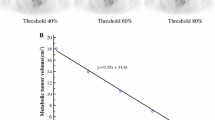

This prospective study was approved by the institution’s Ethics Committee, and all patients provided written informed consent. A total of 50 BC patients at diagnosis underwent PET/MRI before pharmacological and surgical treatment. For each primary lesion, the following data were extracted: morphological data including tumour-node-metastasis stage and lesion size; apparent diffusion coefficient (ADC); perfusion data including forward volume transfer constant (Ktrans), reverse efflux volume transfer constant (Kep) and extravascular extracellular space volume (Ve); and metabolic data including standardized uptake value (SUV), lean body mass (SUL), metabolic tumour volume and total lesion glycolysis. Immunohistochemical reports were used to determine receptor status (oestrogen, progesterone, and human epidermal growth factor receptor 2), cellular differentiation status (grade), and proliferation index (Ki67) of the tumour lesions. Correlation studies (Mann–Whitney U test and Spearman’s test), receiver operating characteristic (ROC) curve analysis, and multivariate analysis were performed.

Association studies were performed to assess the correlations between imaging and histological prognostic markers of BC. Imaging biomarkers, which significantly correlated with biological markers, were selected to perform ROC curve analysis to determine their ability to discriminate among BC subtypes. SUVmax, SUVmean and SUL were able to discriminate between luminal A and luminal B subtypes (AUCSUVmean = 0.799; AUCSUVmax = 0.833; AUCSUL = 0.813) and between luminal A and nonluminal subtypes (AUCSUVmean = 0.926; AUCSUVmax = 0.917; AUCSUL = 0.945), and the lowest SUV and SUL values were associated with the luminal A subtype. Kepmax was able to discriminate between luminal A and luminal B subtypes (AUC = 0.779), and its highest values were associated with the luminal B subtype. Ktransmax (AUC = 0.881) was able to discriminate between luminal A and nonluminal subtypes, and the highest perfusion values were associated with the nonluminal subtype. In addition, ADC (AUC = 0.877) was able to discriminate between luminal B and nonluminal subtypes, and the lowest ADCmean values were associated with the luminal B subtype. Multivariate analysis was performed to develop a prognostic model, and the best predictive model included Ktransmax and SUVmax parameters.

Using multivariate analysis of both PET and MRI parameters, a prognostic model including Ktransmax and SUVmax was able to predict the tumour subtype in 38 of 49 patients (77.6%, p < 0.001), with higher accuracy for the luminal B subtype (86.2%).